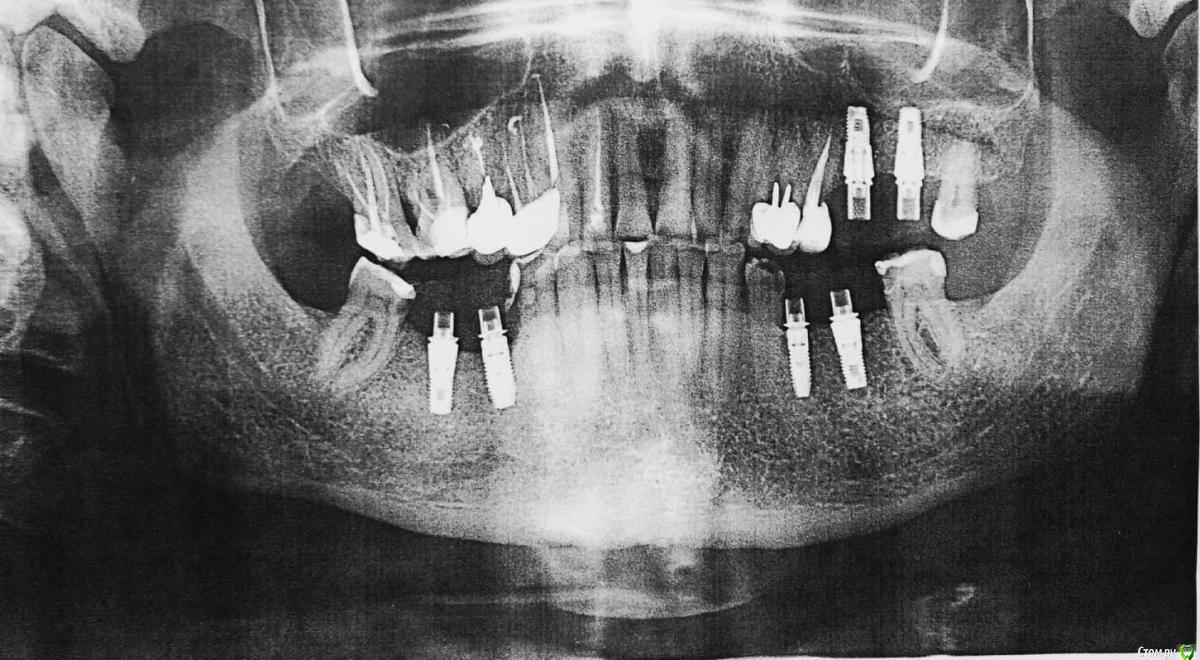

лемурка Опубликовано 29 августа, 2018 Поделиться Опубликовано 29 августа, 2018 Здравствуйте, уважаемые профессионалы! Суть проблемы:Мужу 63 года. Два года назад ему были установлены 6 имплантатов Astra с субгингивальным погружением. Хирург не посчитал необходимым наращивание костной ткани, хотя 6 зуб нижней челюсти справа отсутствовал более 30 лет.Сейчас, когда пришло время установки постоянных коронок, оказалось, что имплантаты на нижней челюсти установлены плохо, торчат над костной тканью, особенно на месте 5 зуба, находящегося рядом с 6 ранее отсутствующим. Шаблоны не применялись. Есть ощущение, что 5 имплантат не совсем в ряду, смещен внутрь. Десны в местах установки 5,6 имплантатов с обеих сторон нижней челюсти впалые и более темного цвета. Цвет десен в месте установки имплантатов на верхней челюсти нормальный, и эффект впалой десны отсутствует. Болей в области установленных имплантатов нет. Предлагаемые варианты решения сложившейся ситуации на сегодняшний момент: Первое мнение:1) Хирург, сделавший имплантацию, признает проблему торчащих имплантов, но предлагает ограничиться пластикой десен 5, 6 зубов с обеих сторон нижней челюсти.Объясняет это тем, что с имплантатами ничего плохого не произойдет, из костной ткани они не выпадут, несмотря на то, что не полностью туда погружены (5 имплантат торчит над костной тканью якобы на 1 мм). А операция по удалению и установке новых - травматичная, с возможностью разных осложнений, как, собственно, и любая операция. Удалять данные имплантаты очень сложно. Предлагает вскрыть десны, обточить инструментом торчащие из костной ткани части имплантатов для удаления остатков прилипших тканей и сверху сделать пластику десен. Это, по его мнению, должно решить проблему попадания пищи и невозможности нормальной гигиены.Из-под десен под имплантатами нижней челюсти при надавливании инструментом появляется в небольшом количестве белое содержимое. Врач характеризует эту субстанцию как смесь десневой жидкости с остатками попадающей пищи. После пластики деснен эта проблема якобы должна исчезнуть. Второе мнение:2) Есть мнение другого врача, который считает, что с костной тканью проблем нет, наращивание ее не требуется (собственно, как и первый хирург), но надо заменить все (!) 4 нижних имплантата на новые с субкрестальным погружением другой фирмы, штрауман, также добавив пластику десен с двух сторон. Врач объясняет наличие выделяемой белой субстанции неким воспалительным процессом не в костной ткани, но тем не менее также требующим кардинального решения удаления имплантатов. Вопрос:Опуская материальную сторону, хотелось бы услышать ваше компетентное мнение по сути проблемы. Как поступить правильно? В принципе готовы далее заниматься исследованием ситуации и посетить еще врачей, но, как видите, уж очень разные подходы к решению проблемы. Неспециалисту сложно принять взвешенное решение, поэтому хочется услышать максимальное количество согласий с одним из мнений или услышать ваше. Возможно, есть еще какие-либо варианты ? Я в шоке, если честно. Спасибо. Р.S. Хирург - имплантолог выбирался долго, и был не из дешевых.(( Привожу снимки августа 2016-ого года (сразу после установки) и 2018-ого года. Ссылка на комментарий

лемурка Опубликовано 1 сентября, 2018 Автор Поделиться Опубликовано 1 сентября, 2018 Врач, предлагающий удаление, считает, что имплантаты установлены неправильно. Они действительно ( 5 особенно явно) не погружены в костную ткань, торчат над ней. В связи с этим нарушена физиология: правильное взаимодействие костной ткани, десны и имплантатов. Результат - впалые десны, выделяющаяся белая суспензия. Это плохо, особенно последнее.Нужны имплантаты другой системы с углубленной установкой (например, штрауман). Вообще объяснялось,что имплантаты должны быть погружены с некоторым углублением (это я уже в интернете прочитала, что можно иначе в случае с астрой, уж не знаю, верно ли) Наконец, невозможно сделать правильные коронки. В данном случае они будут как бы парить над десной. Будет все время попадать пища. Ссылка на комментарий

Nazim_NV86 Опубликовано 7 сентября, 2018 Поделиться Опубликовано 7 сентября, 2018 не вижу показаний к удалению+11мм не проблема. Ссылка на комментарий

лемурка Опубликовано 7 сентября, 2018 Автор Поделиться Опубликовано 7 сентября, 2018 (изменено) +11мм не проблема.Nazim, это врач говорит, что выступает на 1мм. На снимках длина всего имплантата равна 11мм ( все четыре имплантата имеют такую длину), судя по паспортам, нам переданным. Может, там и 2 мм...Ситуация на данный момент - врач, установивший имплантаты, настоятельно советует пересадку десны ( для начала с правой стороны) и то, что меня смущает больше всего - шлифовку выступающих над костной тканью имплантатов.К сожалению, никто из врачей не написал, насколько эта процедура правильна, распространена в такой ситуации и решает проблему скапливания микробов вокруг имплантата в зоне, выступающей над костной тканью. Есть смысл ее делать? Врач утверждает, что десна не сможет приклеиться к имплантату, и поэтому необходимо сделать эту шлифовку, чтобы уменьшить существование в этой области микробов(( Кто-нибудь практикует такую шлифовку? Имеет смысл ее делать? Насколько это реально отшлифовать эту часть, если она составляет 1-2 мм? После такой некачественной установки имплантатов не очень доверяю этому врачу(( Изменено 7 сентября, 2018 пользователем лемурка Ссылка на комментарий